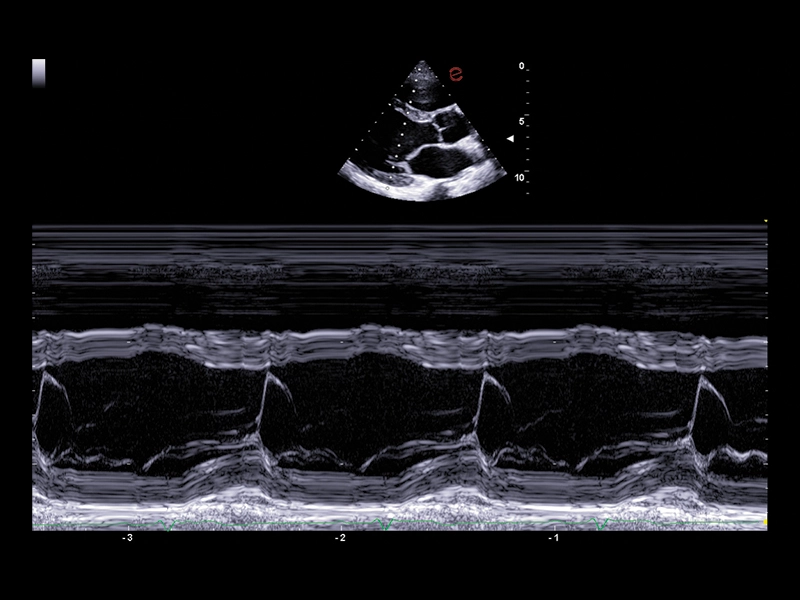

MyLab™C30 - Bmode - Plax

MyLab™C30 - Bmode - Plax